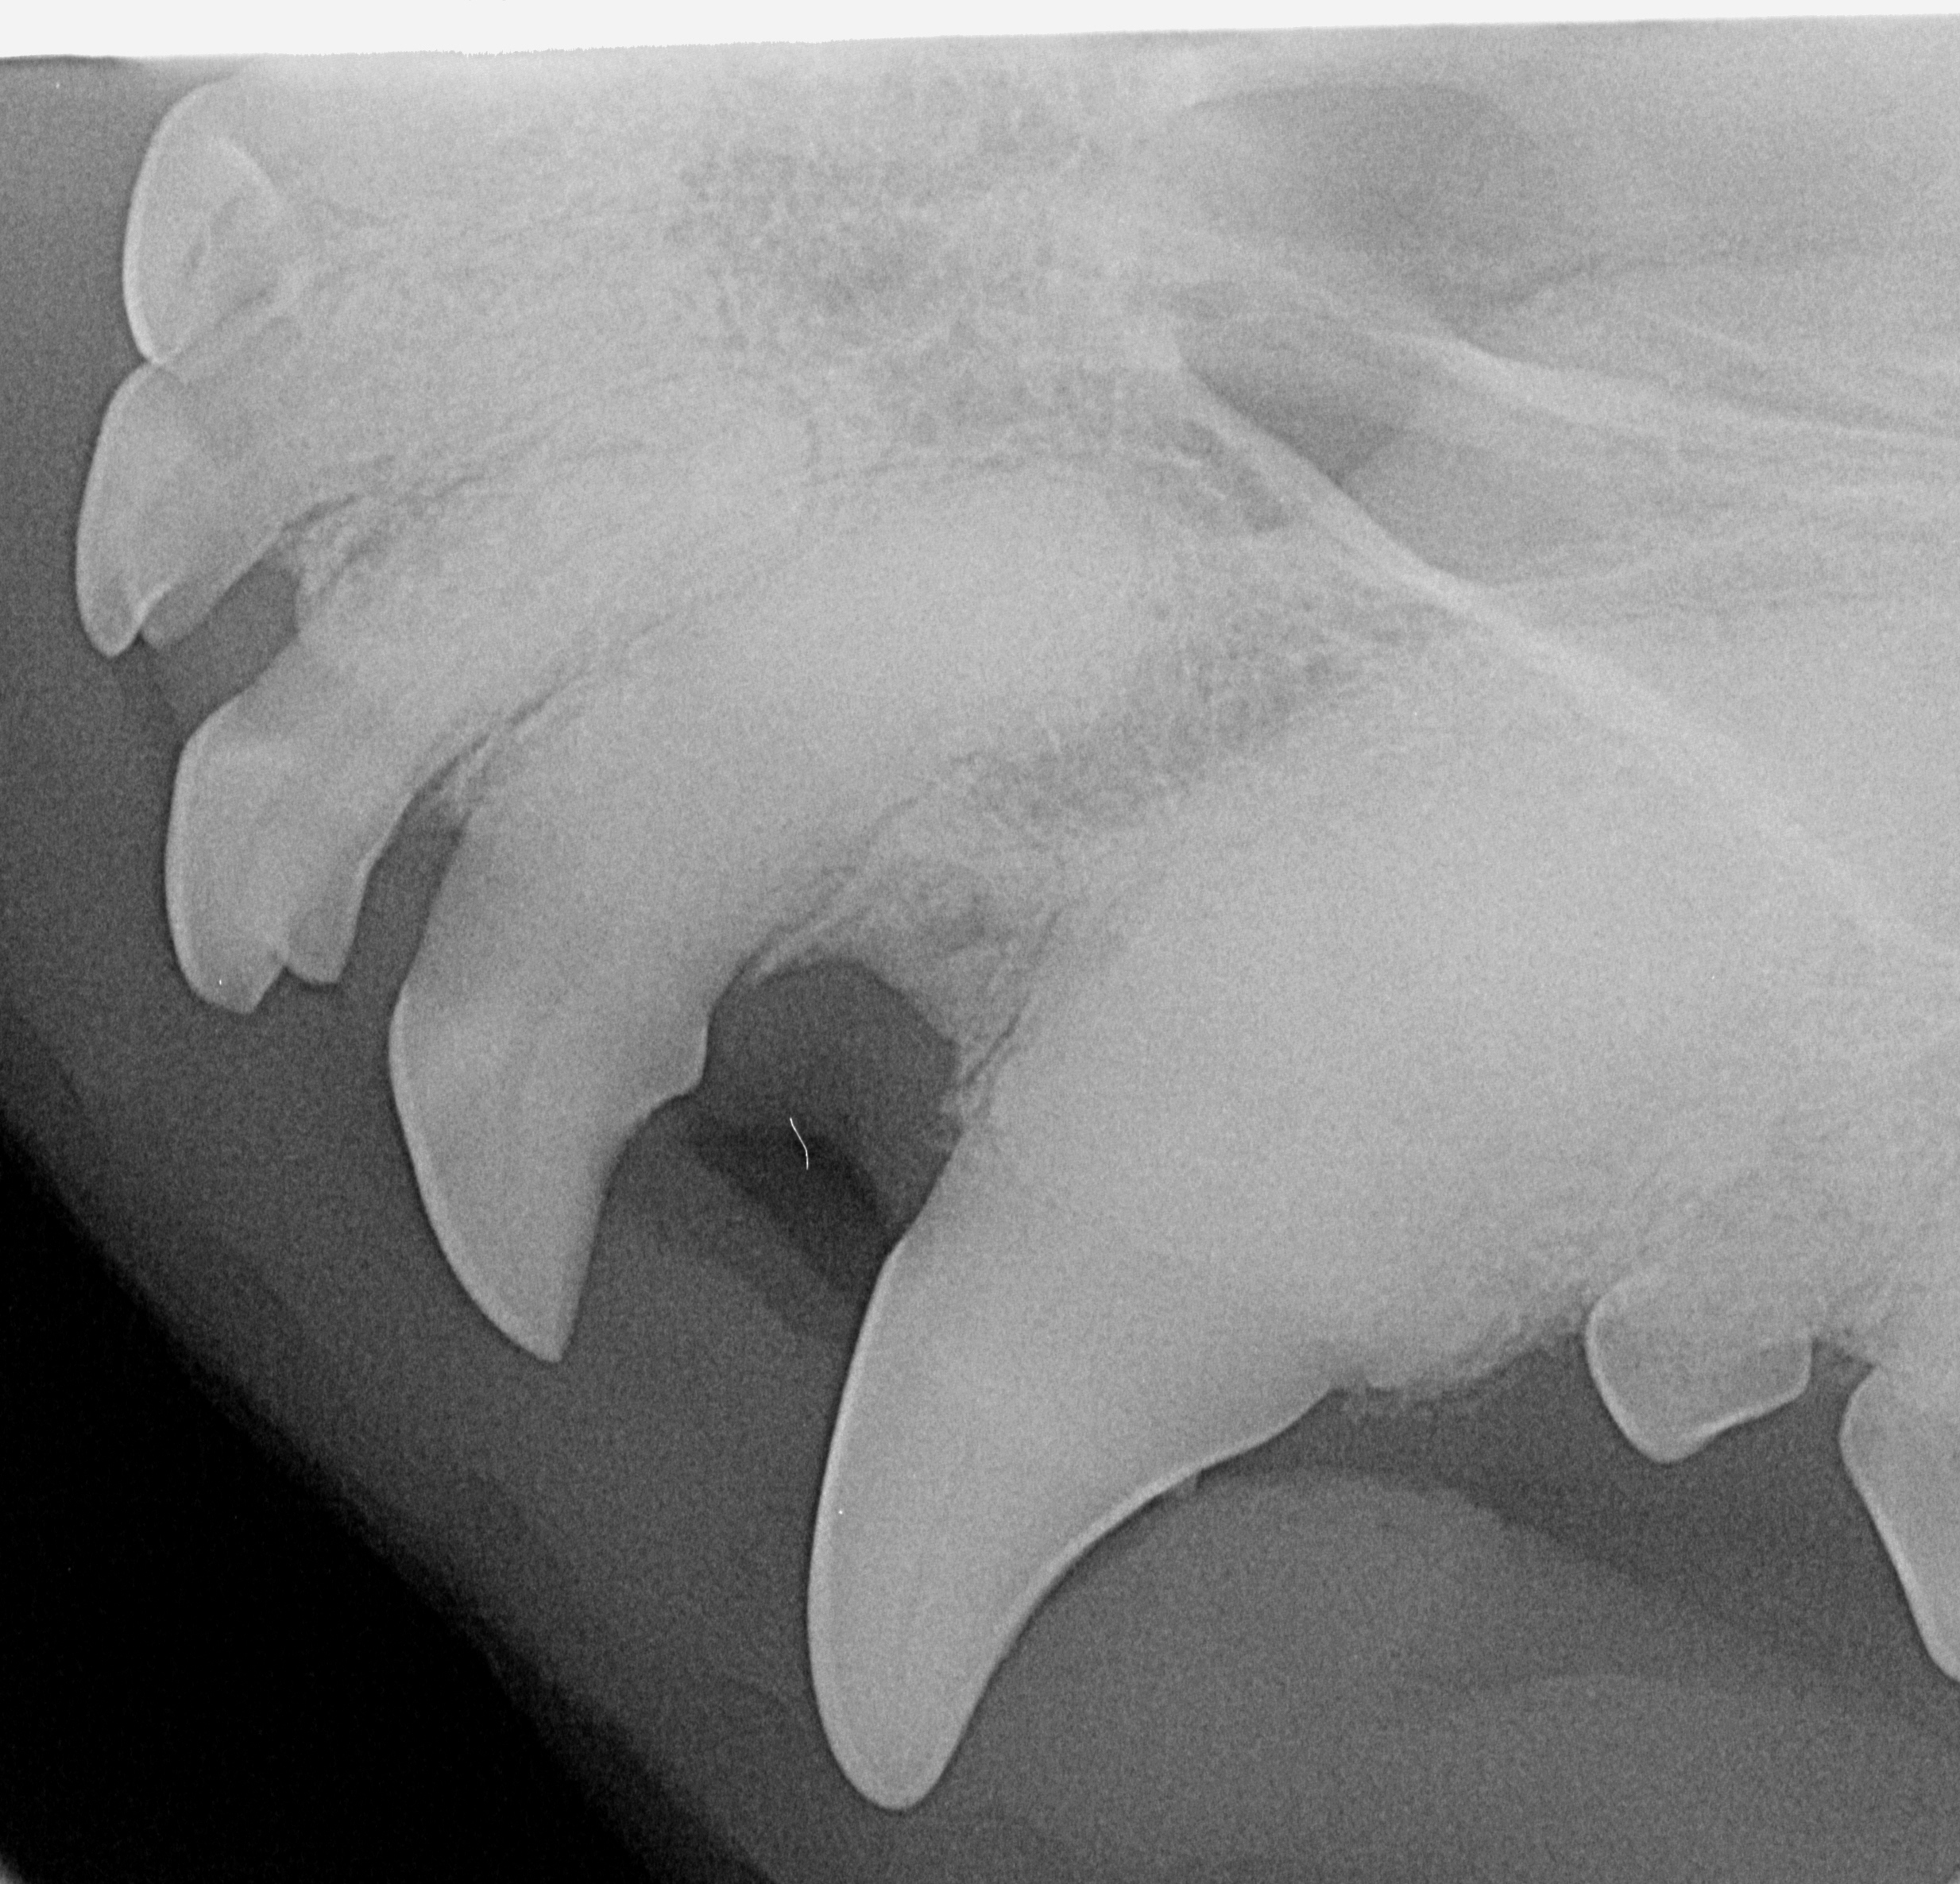

In vielen Fällen ist es ratsam, sich die Zähne in Narkose nicht nur von außen zu betrachten, sondern von ihnen samt Zahnwurzeln Röntgenbilder anzufertigen, um eine ganz differenzierte Beurteilung und

Behandlung vornehmen zu können. Dies ist mit unserem Dentalröntgen für all unsere Kleintiere, also Hunde, Katzen,kleine Heimtiere, Exoten usw. bestens möglich. Weitere Informationen finden Sie unter Leistungen „Zahn und Zahnfleischbehandlungen“.